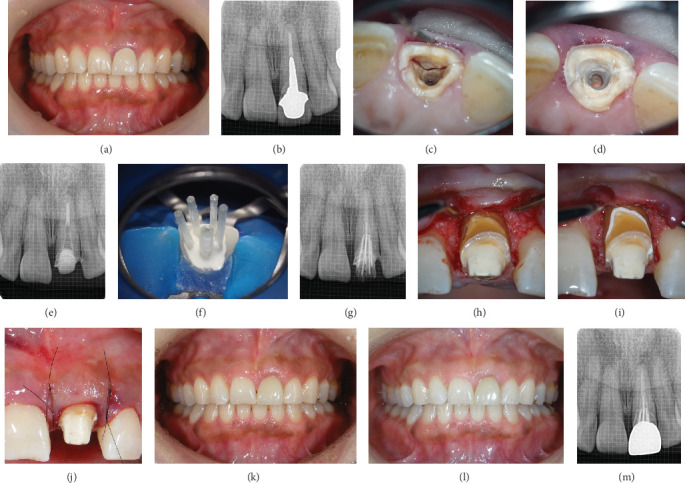

Objective: The aim of this study is to present cases of root preservations in which minor surgery and characteristic multifiber foundation were performed to treat maxillary central incisor root fractures near the bone margin. Clinical Considerations: Two patients experienced root fractures of the central incisors due to short- or long-term trauma. Orthodontic extrusion was not employed in both cases; instead, minimal periodontal surgery was performed as pretreatment. In cases where the patient's tooth remained intact, fractured pieces were bonded. However, in cases where the root of the tooth was fractured with the prosthesis, a new restoration was fabricated. The roots were constructed using multiple characteristically placed glass fiber posts and materials with high biocompatibility and hydrophilicity as the foundation. Fractured teeth were esthetically restored using conservative or prosthetic treatment methods, resulting in patient satisfaction. No complications were observed at the 4-year follow-up. Conclusions: Although horizontal root fractures near the alveolar bone are generally considered to have a poor prognosis and esthetic outcome, they can be restored esthetically with minimal invasion by selecting appropriate procedures and materials.

Abstract Image